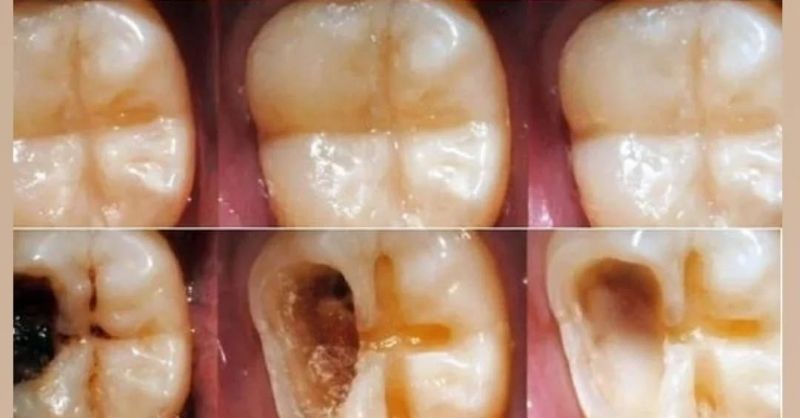

Eating Well and Taking Care of Your Teeth

Are you fed up with the discomfort and hassle that come with cavities? You’re not alone — and the good news is, there are simple, natural ways to...